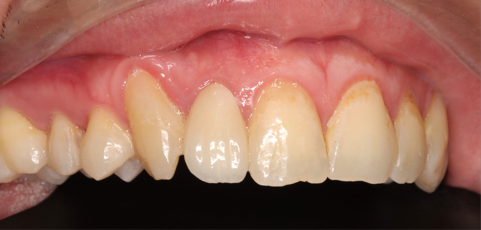

1/16/2025: All-ceramic crown restoration for #12; patient asymptomatic